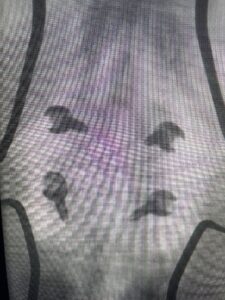

Fig 3: Lateral and AP fluoroscopic images demonstrating placement of pedicle screws for L4-5 fusion for spondylolisthesis.

Fig 6: AP and lateral fluoroscopic images demonstrating pedicle screw placement in L3-4 fusion for spondylolisthesis.